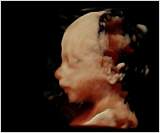

Aufgrund einer hohen technischen Ausstattung in meiner Ordination ist es mir möglich ein dreidimensionales Bild von Ihrem Kind anzufertigen. Die Kindsbewegungen können „live“ am Bildschirm mitverfolgt werden (4D).

Dieses ermöglicht einerseits die bessere Diagnostik einiger Fehlbildungen wie etwa der Lippen-Kiefer-Gaumenspalte, andererseits kann so das erste "Foto" von Ihrem noch ungeborenen Kind gemacht werden, was die Mutter-Kind-Beziehung zusätzlich fördert und sicherlich eine nette Erinnerung an diese außergewöhnliche Zeit ist.

Ein 4-D-Bild |